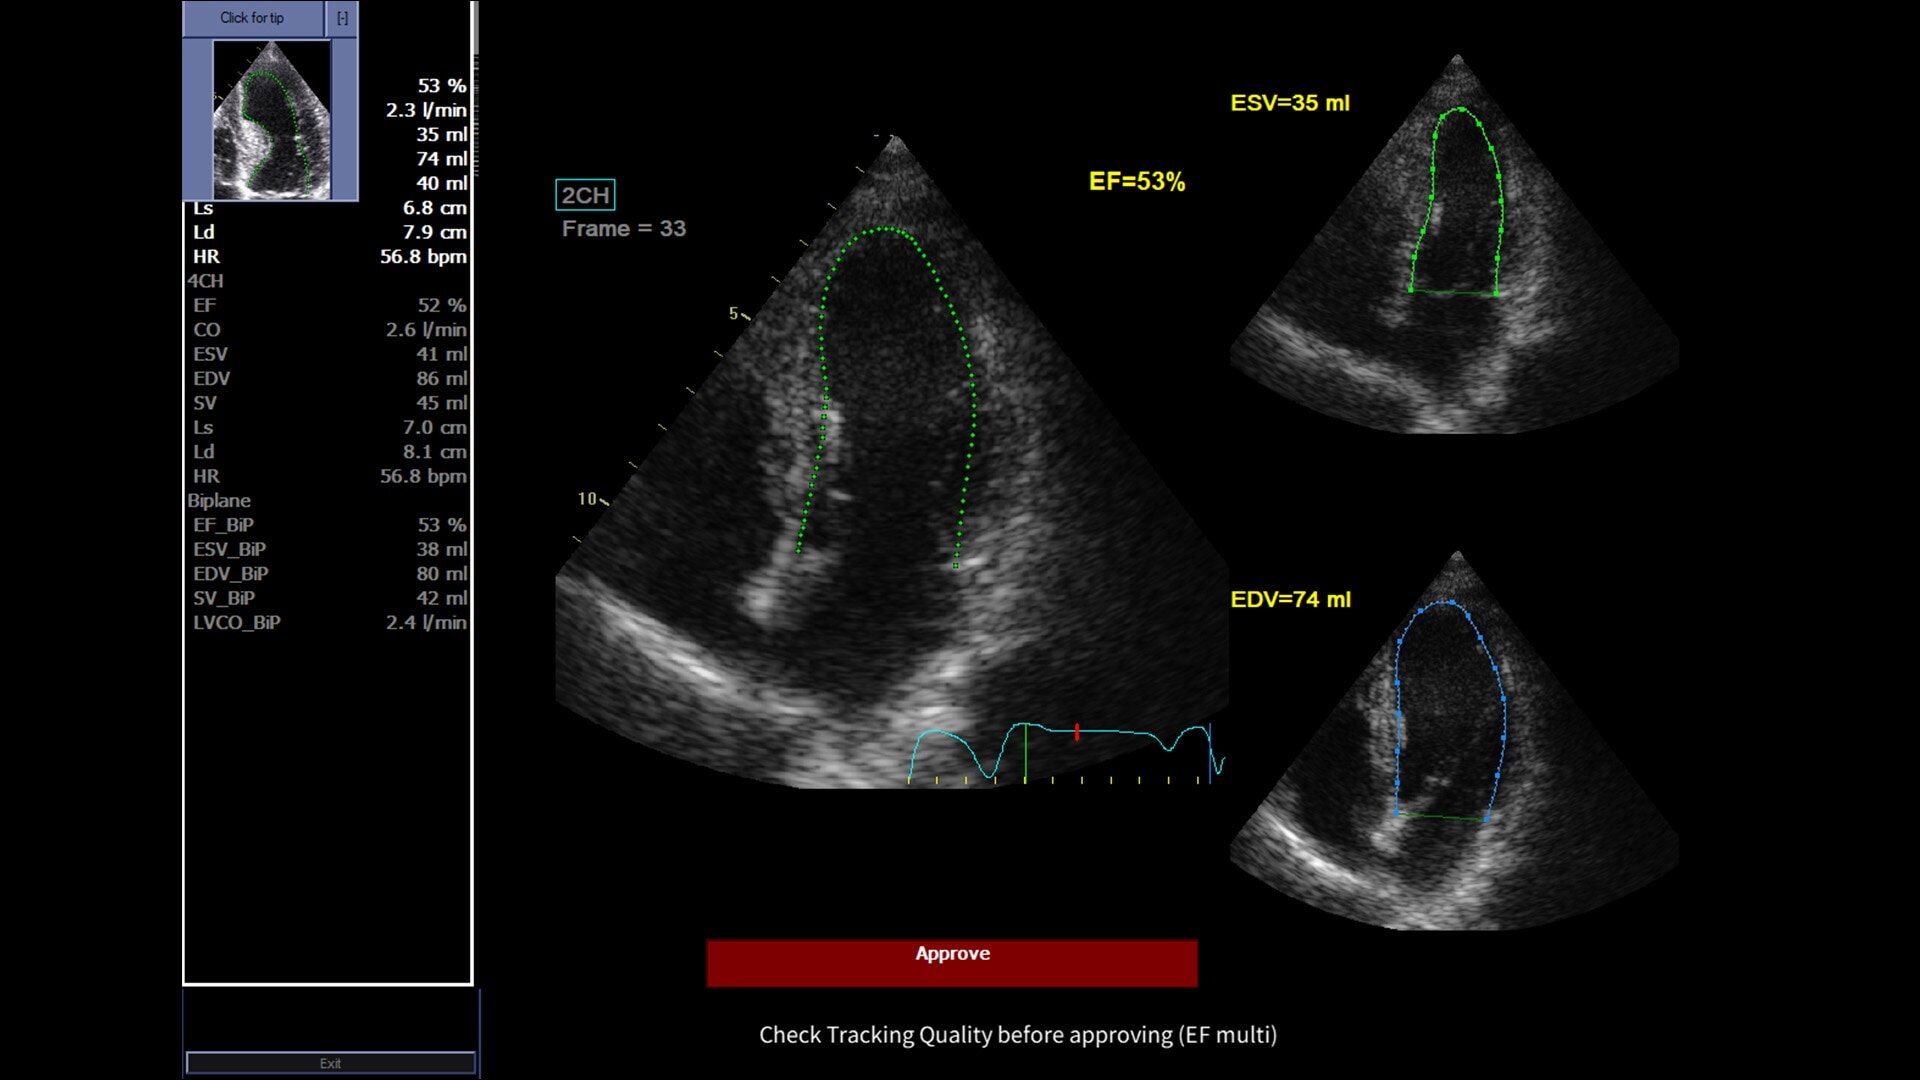

Powered by VisionBoost Architecture, Versana Premier provides optimal image quality so users can easily reach a diagnosis. Advanced clinical features help address challenging cases while automated tools help reduce scan time:

• Optimize images while scanning with Whizz clinical features, easily improve Color Doppler with Whizz Color Flow, and view scans in the image style that suits your preference with Whizz Easy Style

• Make automated 2D Measurements and Volume Calculations with Auto Contour, Auto Bladder, Whizz Follicle and Auto-IMT